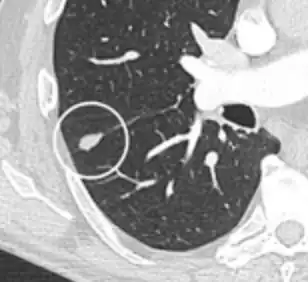

-

Low attenuating nodule (in this case a fat containing hamartoma).[9] -

Cavitation with relatively thick wall, in this case aspergilloma).[9]